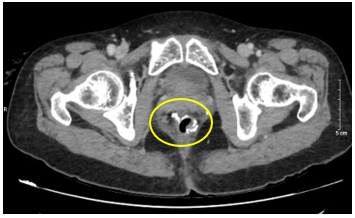

– CT scanner ổ bụng : chưa phát hiện hình ảnh tái phát tại miệng nối

Hình 4: Hình ảnh miệng nối đại–trực tràng qua CLVT, miệng nối thông tốt, không ghi nhận rò rỉ/ bục miệng nối, không có tụ dịch, không thấy khối bất thường choán chỗ.